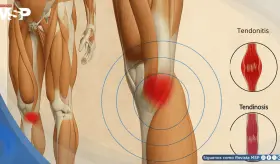

Aunque suelen confundirse, la tendinitis es un proceso inflamatorio agudo, mientras que la tendinosis es una degeneración crónica del tendón, mucho más común y con un abordaje terapéutico diferente.